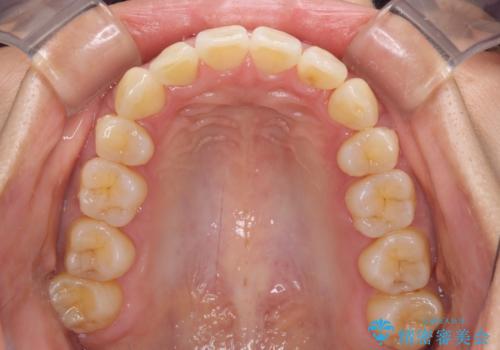

前歯のデコボコを治したい 費用を抑えた抜歯矯正

- 上下前歯のでこぼこを気にされ、矯正治療を希望された患者様です。

費用を抑えるため、メタルブラケットを採用し、抜歯矯正を行うこととしました。

通常であれば、上下顎左右小臼歯各1歯の合計4本を抜歯しますが、歯肉退縮の著しい下顎前歯を抜歯して欲しいという患者様の強い希望により、上顎のみ左右小臼歯2歯を、下顎は前歯を1歯を抜歯することとしました。

抜歯する歯を変更したため奥歯の咬合はアンバランスとなりましたが、前歯は綺麗に整い、歯肉退縮も回避できました。